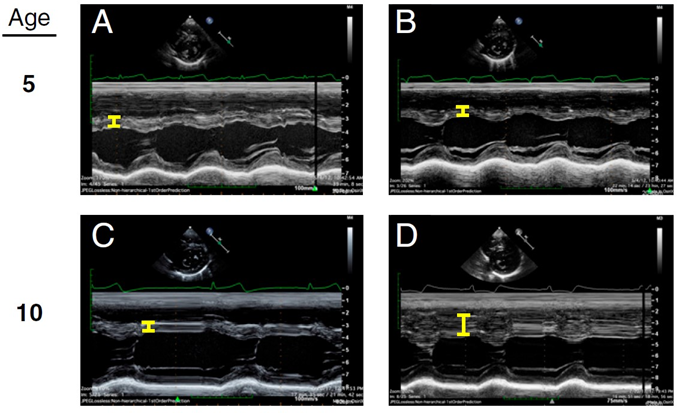

17b) For example: identical twins with a positive genetic diagnosis of #HCM underwent #echocardiography at the age of 5 years. Septal thickness was normal in both, but five years later, one--& only one--of them developed septal hypertrophy.

See 🔓pubmed.ncbi.nlm.nih.gov/33658374/

17c) Another: Variable phenotypic expression in the offspring of a ♂️w/ #HCM + for #MYBPC3 mutation. 3 of 4 siblings are also carriers. ♂️ B develops massive septal hypertrophy, ♀️ C shows limited hypertrophy, & ♀️ D has normal LV.

🔓 pubmed.ncbi.nlm.nih.gov/31864978/